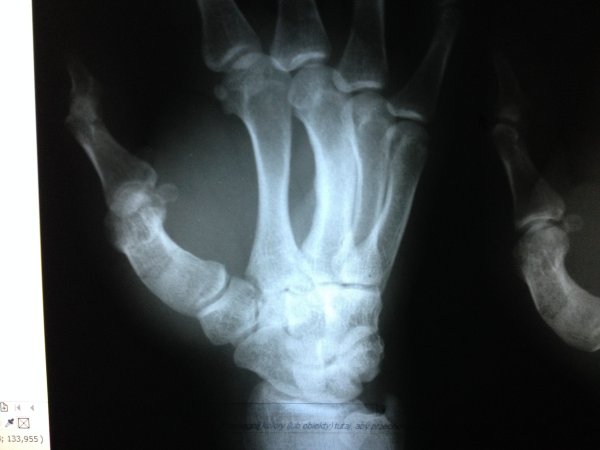

DOKUMENTACJA MEDYCZNA GAMROTA I WŁODARKA

Dokumenty dotyczące kontuzji zawodników KSW.